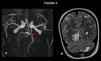

Figura 2. Estudio de angiografía por resonancia magnética de troncos supraaórticos tras contraste intravenoso. A) Variante anatómica que explica la ausencia de infarto en el territorio cerebral posterior izquierdo: un origen «fetal» de la arteria cerebral posterior izquierda (flecha), con salida directa de la carótida, que asocia un segmento P1 hipoplásico (punta de flecha). B) Secuelas de infartos en el territorio de la arteria cerebral posterior derecha, con áreas de necrosis laminar y gliosis e infarto en el territorio de la arteria cerebelosa posteroinferior izquierda. Había otro infarto en el territorio de la arteria cerebelosa posteroinferior derecha que no se aprecia en la imagen 2B pero sí en otros cortes.